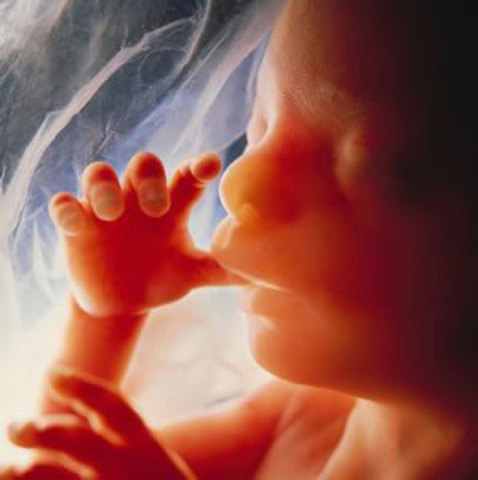

• Semana 15 y 16

Semana 15 y 16

Al finalizar el cuarto mes mide entre 15 y 20 cm y pesa de 120 a 200 gr, aparecen las cejas, pestañas y pelo en la cabeza (lanugo) que desaparecerá entre el octavo y noveno mes. El producto comienza a mover sus articulaciones.

La piel es transparentes, los huesos y tejido muscular continúan desarrollándose y los huesos se hacen más duros.